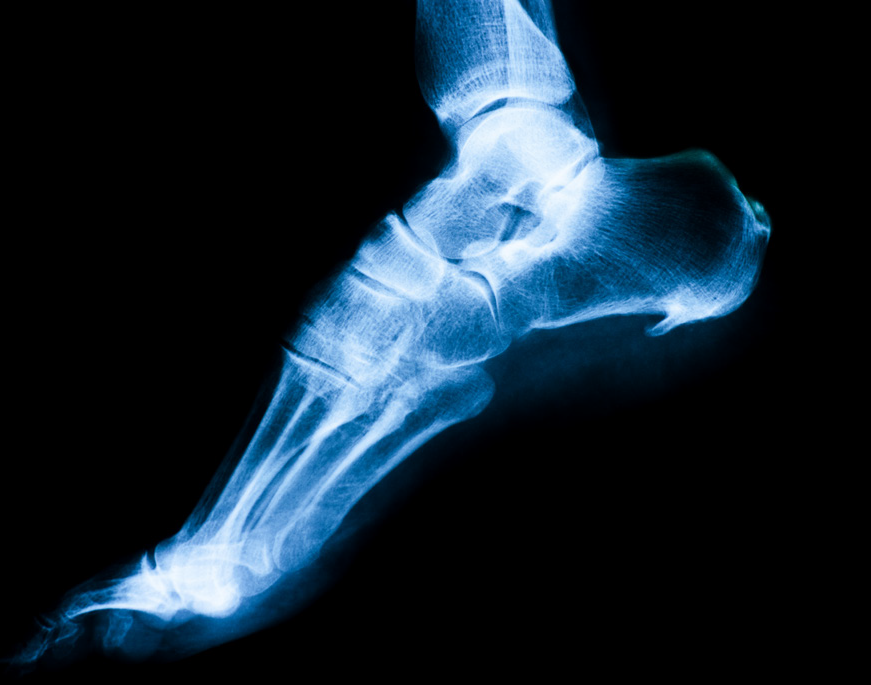

□ 임상적인 증상과 이학적 검사, 촉진 등에 의해 진단할 수 있습니다.

□ 때로는 X-ray에서 종골의 골극을 발견할 수 있습니다.